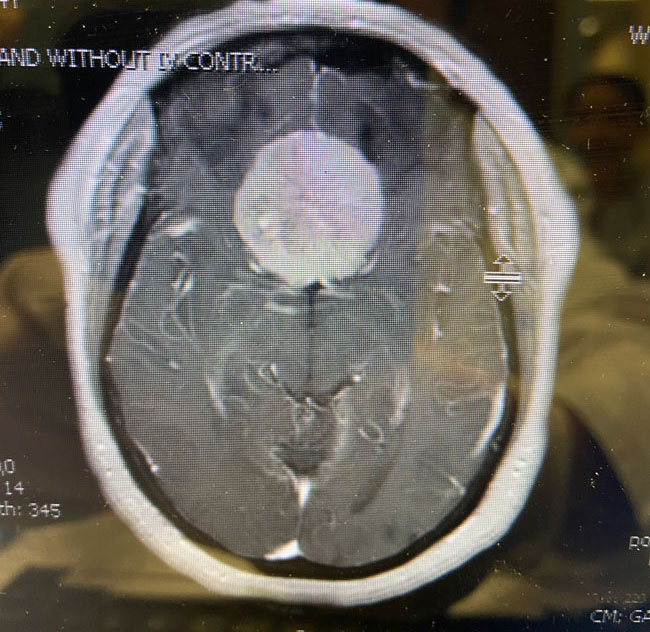

This is a 64 year-old woman with no significant past medical history who noted rapid deterioration of vision in her left eye 3 weeks earlier. She said it felt like there was a cloud over her eye. Ophthalmology evaluation confirmed poor vision in the left eye and ordered a brain MRI. The MRI demonstrated a large planum sphenoidale meningioma with significant compression on the optic nerves and optic chiasm and significant surrounding edema (Figures 1 a, b, and c). She was then referred to Dr. Michael Brisman for neurosurgical evaluation.